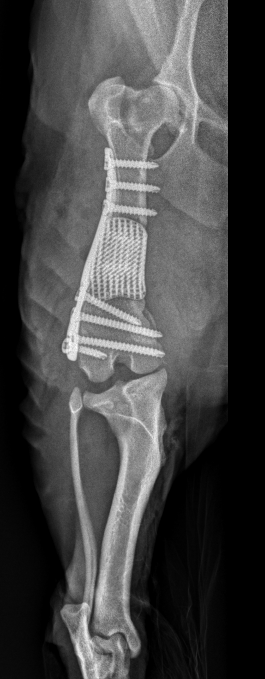

在没有标准解决方案的情况下,麦基博士聘请了皇家墨尔本理工大学先进制造部门的技术主管米兰·布兰特教授,他和博士后研究员达潘·希迪德博士一起,用专业知识来帮助。他们用目前治疗人类骨病的新一代植入物的研究成果,利用辖区内的3D金属打印技术,为西摩设计并制造了一种定制的、基于晶格的钛植入物。

布兰特教授说:“在检查了西摩的CT扫描后,我们设计了一个坚固的晶格结构,可以支撑他的体重,并将其固定在一个定制的、与他畸形骨骼完全吻合的钢板上。晶格填充了骨缺损,使股骨恢复到正常长度和排列,同时在股骨愈合时允许新骨生长,最终植入物成为愈合骨的一部分。”

当西摩从皮肤和牙齿疾病中恢复过来的时候,麦基博士和她的团队进行了先进的外科手术来安装植入物。她说:“为了鼓励骨骼生长到晶格中,从西摩的肩膀上切下了一块骨移植。“这是混合了犬脱钙骨和西摩自己富含血小板的血浆,然后压入骨板的晶格然后将骨格和钢板放入西摩左股骨骨缺损处,并固定到位。”